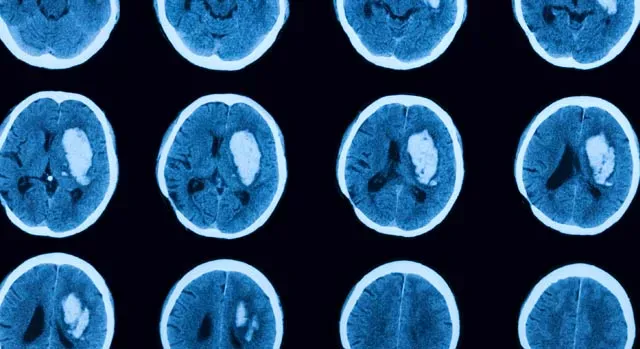

Реабілітація при інсульті починається після першої екстреної допомоги. Завдання лікарів – правильно діагностувати стан, щоб визначити тип та масштаби крововиливу. Далі призначається комплексна медикаментозна, інвазивна терапія, мета якої – локалізувати прорив та зберегти життя пацієнту. Що таке інсульт? Це патологія мозкового кровообігу, що раптово виникла, яка триває більше доби. Саме тривалість відрізняє інсульт від класичної транзиторної ішемії, симптоматика якої зникає протягом кількох годин. У групі ризику – люди, які страждають на артеріальну гіпертонію, патології серцевого ритму, а також ті, хто переступив віковий рубіж у 50 років. Визначити інсульт можна миттєво з порушенням мовних, рухових, когнітивних та інших функцій. Щоб не запустити процес деградації тканин, лікарі рекомендують починати відновлення при інсульті відразу після кризи. Чому? Внаслідок згубного механізму (блокування кровотоку або крововиливу) помирає частина мозкових клітин, зокрема, відповідальних за вербальну, пізнавальну активність. Цінна кожна хвилина! За принципом виникнення, розрізняють такі види інсульту:

Ішемічний інсульт трапляється тоді, коли людина спить, а геморагічний – при надмірному фізичному навантаженні, внаслідок стресу. Симптоми інсультів подібні: м'язова слабкість, запаморочення, нудота, порушення координацій руху, різка втрата зору, проблеми ковтання. В особливо важких випадках людина втрачає свідомість і впадає в кому, яка може тривати кілька місяців. Догляд за лежачим хворим після важкого інсульту передбачає низку медичних заходів, виконання яких є обов'язковим. Погіршують ситуацію проблеми, що виникають внаслідок нерухомості тіла: застійні процеси в тканинах, пролежні, слабка вентиляція легень і т.д.